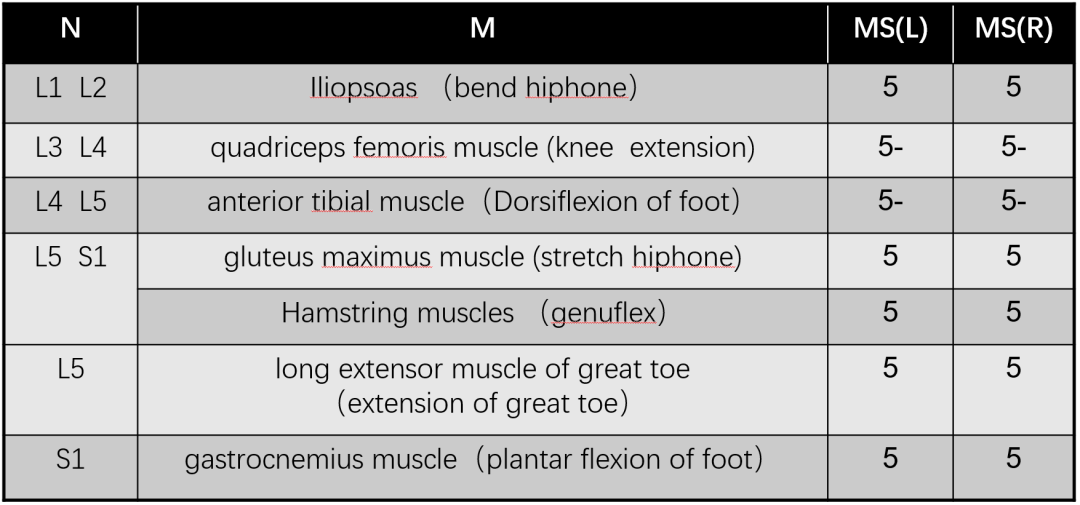

男,76岁

现病史:

腰背痛2年,加重伴腰部后凸不能直立半年

Diagnosis:

腰椎侧后凸畸形

腰椎陈旧性压缩性骨折(L4)